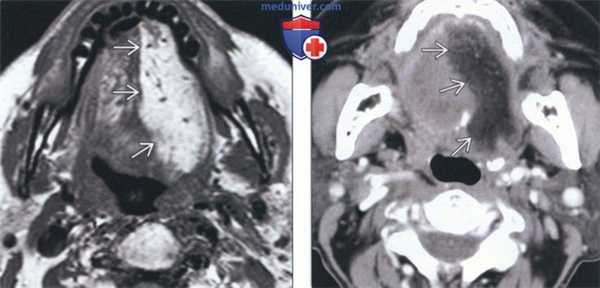

(Слева) МРТ Т2ВИ, аксиальная проекция. Денервация языка в острую стадию. Выраженный отек половины языка с повышением интенсивности сигнала. Обратите внимание на четкую демаркационную линию. Денервация была обусловлена переневральным ростом опухоли вдоль ЧН XII.

(Справа) МРТ Т1ВИ FS с КУ, подострая денервация языка. Накопление контраста в мышцах левой половины языка. Обратите внимание на четкую границу между половинами. Причиной денервации стало метастатическое поражение основания черепа, в том числе подъязычного канала.

(Слева) МРТ Т1ВИ. Хроническая атрофия языка с выраженным повышением сигнала от левой его половины, которое характерно для жировой атрофии. Причиной паралича являлась параганглиома яремного отверстия (не показана).

(Справа) КТ с КУ, аксиальная проекция. Жировая атрофия вследствие хронической денервации левой половины языка. Правая половина языка выглядит крупнее левой, ее можно принять за опухоль. Как оказалось, причиной денервации является деструктивная костная опухоль на уровне подъязычного канала.